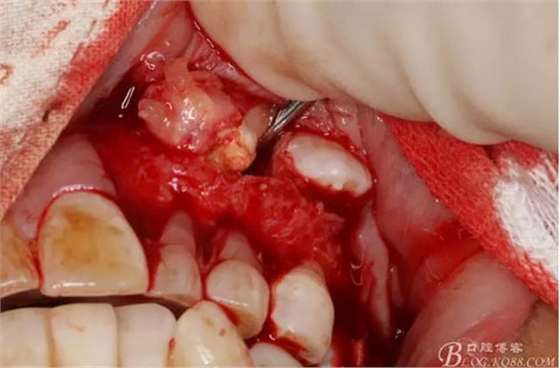

圖12.用小骨鑿去除覆蓋在牙瘤表面的骨質(zhì)。發(fā)現(xiàn)牙瘤的包膜。

圖13.暴露出部分牙瘤

圖14.沿一側(cè)骨壁逐步剝離牙瘤組織。